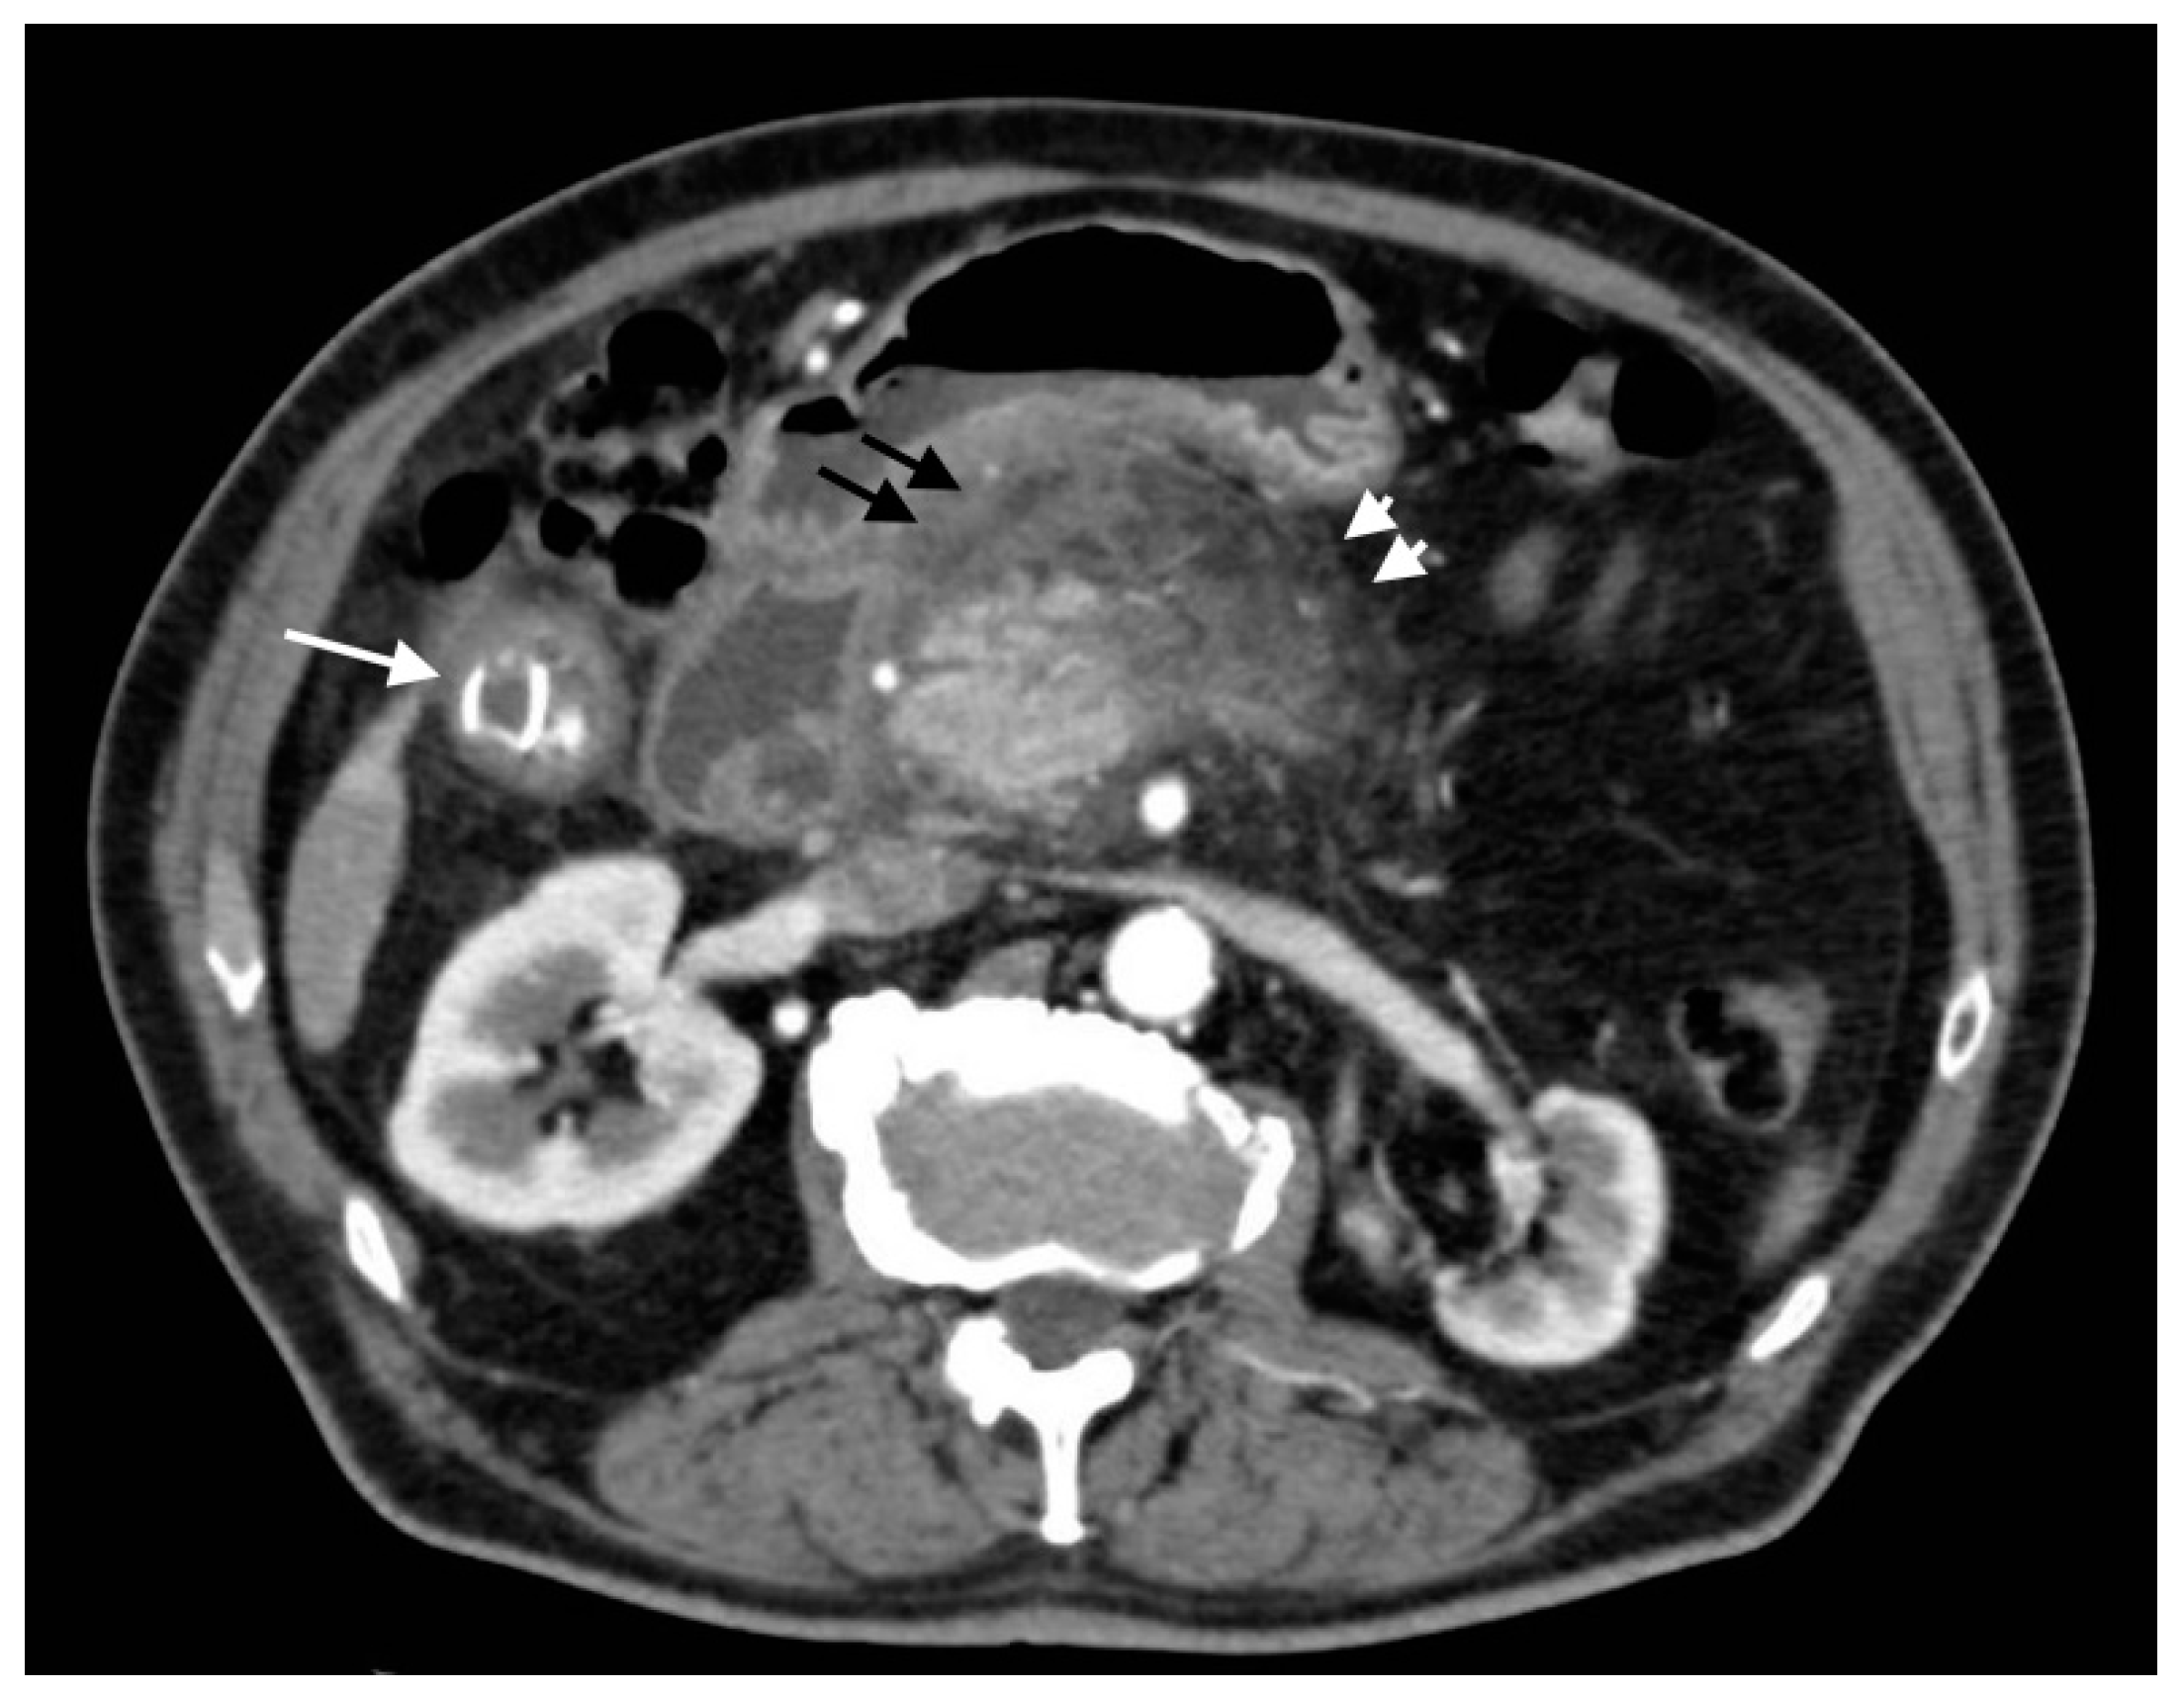

Figure 14.

Acute calculous cholecystitis with pancreatitis (biliary pancreatitis): axial scan shows an acute cholecystitis (white arrow) with edematous hypoattenuating pancreatitis with surrounding peripancreatic fat strands (arrowheads) and fluid (black arrows).